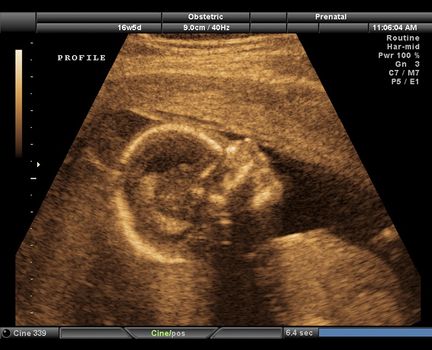

Ultrasound scan images reveal harmful effects of smoking during pregnancy

The harmful effects that smoking has on babies in the womb may be seen using 4D ultrasound scans, according to new research conducted by Durham and Lancaster University.

Studying the scan images, Dr Nadja Reissland monitored 20 mums attending the James Cook University Hospital in Middlesbrough, four of whom smoked an average of 14 cigarettes a day. After looking at their scans at 24, 28, 32 and 36 weeks, she detected that foetuses carried by women who smoked continued to show significantly higher rates of mouth movement and self-touching than those carried by non-smokers. This kind of movement in the womb tends to happen less frequently as more control is gained closer to birth; indicating that babies carried by women who smoke may have delayed development of the central nervous system.

The images, which show thousands of tiny movements in unborn babies faces, could be used to encourage mums to give up smoking if they are struggling to do so.